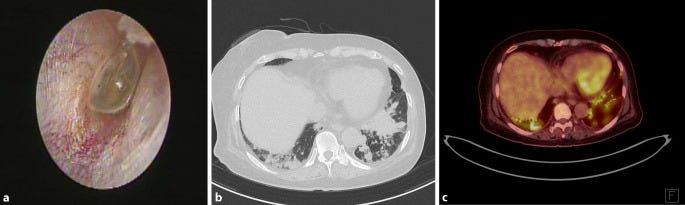

Regarding hyperemia in both eyes, slit-lamp examination was performed, showing conjunctivitis. Tympanometry was performed for the ear fullness sensation, and bilateral otitis media with effusion was confirmed (Fig. 1a).

a tympanogram of the left ear with effusion of tympanic membranes; b computed tomography (CT) image of the chest showing variable sized enhancing nodules in both lungs, with lower lung zone predominance; c positron-emission tomography/CT image

Chest computed tomography (CT) imaging revealed enhancing nodules of variable sizes in bilateral lungs; the nodules were predominantly observed in the lower lung zone, suggesting atypical pneumonia or pulmonary metastasis (Fig. 1b). Empirical antibiotic therapy was initiated for managing pneumonia. Positron-emission tomography/CT was performed for the differential diagnosis of the pulmonary lesions; the findings showed inflammatory changes suggestive of vasculitis rather than metastasis (Fig. 1c).